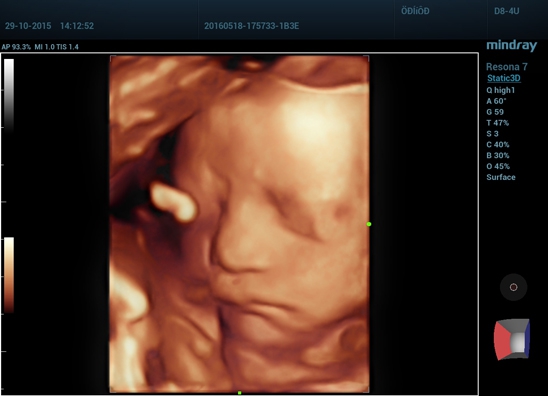

• получение трехмерного изображения с помощью объемных датчиков (Static 3D);

• получение трехмерного изображения в реальном режиме времени (4D);